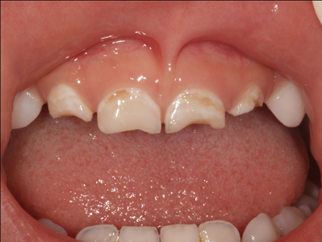

선천성 반사반응 중의 하나인 손가락 빨기는 아이의 정서 안정확보 수단으로 알려져 있다. 아이는 손가락을 빨면서 환각과 유사한 euphoria(일종의 행복감)를 경험한다. 심리 만족을 위해 활용되는 손가락 빨기를 부모가 억압적으로 제한하면 애정결핍 혹은 정서 불안이 유발될 수 있다. 그런데 손가락 빠는 습관이 고착화되어 4세가 넘어서도 계속된다면 치의학적으로 문제가 생긴다. 위의 앞니가 입술 쪽으로 기울어지면서 돌출이 되고 아래 앞니가 혀 쪽으로 기울어지면서 전방부 개방교합이 생길 수 있다. 즉 위 아래 치아의 맞물림이 제대로 되지 않게 된다. 골격 성장의 양태에도 악영향을 준다. 구강 안쪽으로 음압이 생기면서 볼 근처에 있는 근육들이 수축하게 되면 위턱의 치열궁 형태가 좁아지고 치열의 총생(crowding)(*)이 생긴다. 위턱 성장의 직접적인 영향을 받는 아래턱도 후퇴되어 돌출된 안모가 도드라진다. 혀의 위치도 정상보다 후방으로 이동하기 때문에 삼킴 작용에도 영향을 미칠 수 있다.

일반적으로 대부분의 아이들은 4세 정도가 되면 손가락 빠는 습관을 멈춘다. 그런데 6세가 넘어서도 습관이 없어지지 않으면 위험하다. 치의학계도 4세 이후의 손가락 빨기 습관은 구강 구조의 비가역적 변화를 유발한다고 말한다. 즉 교정 치료에 의해서 정상 범위로의 조정이 가능하다고 보는 것이다.

KakaoTalk_20180520_092357131.png